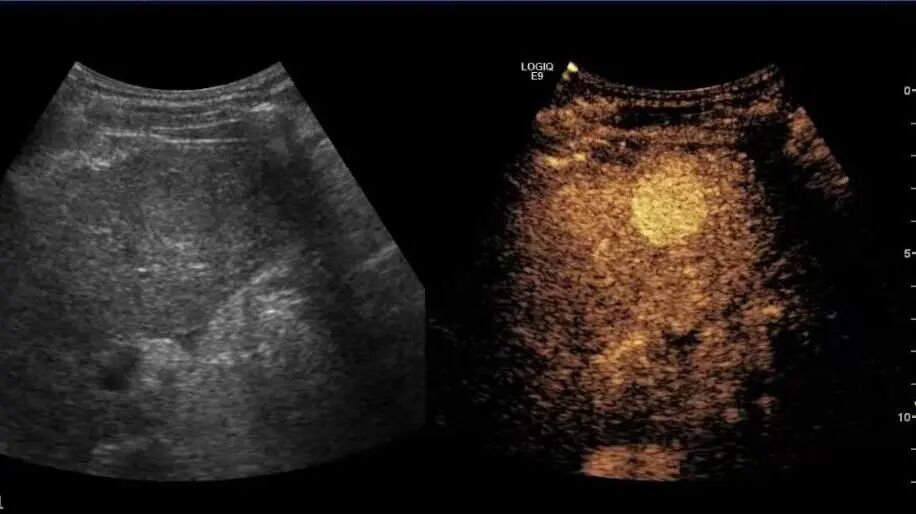

多年来,贵州航天医院各科室紧跟医学前沿,不断强技术、补短板,大力开展新技术、新项目,完成了许多高精尖、高难度、本地区“首例”的技术,填补了医院医疗技术空白,满足了群众日益增长的医疗需求。 复杂性双胎超声监护耗时耗力,技术难度大,风险高,为填补本地区复杂性双胎的超声监护技术空白,我院超声科在遵义市率先开展了此项技术,有效满足了双胎孕妇产检需求,保障了双胎新生儿的平安健康。 本期,我们将为大家带来超声科特色技术——复杂性双胎的超声监护。 案例分享 案例一 28岁的孕妇,自然受孕,怀有单绒毛膜双羊膜囊双胎(MCDA),在我院定期产检的过程中,孕32周超声检查发现两个胎儿的大脑中动脉血流流速(MCA-PSV)相差>0.7倍数的正常值(MoM),高度怀疑发生了双胎贫血红细胞增多序列征(TAPS)。为进一步明确诊断,产科立即组织超声科、手术室、新生儿科等科室进行多学科会诊(MDT),诊断为:双胎贫血红细胞增多序列征(TAPS),在征得孕妇及其家属的同意后,决定提前分娩,及时保障了两名胎儿的生命和健康。 双胎大脑中动脉血流 双胎贫血红细胞增多序列征(TAPS) 案例二 一名26岁的孕妇,是完全双角子宫,且为左侧子宫妊娠,怀有单绒毛膜双羊膜囊双胎(MCDA),一直在我院规律产检,孕16周时,超声检查发现双胎生长不一致,体重相差超过25%,考虑子宫畸形合并早发选择性胎儿宫内生长受限。孕妇在咨询相关上级医院专家后,得到减胎的建议,又前来我院咨询,在我院超声科和产科的合作下,查阅了大量文献、认真评估检查报告后,建议孕妇继续双胎妊娠。在规律、严密的超声监护下,双胎除体重差异外未出现严重胎儿并发症,在34周进行了分娩,截至目前,新生儿生长发育均正常。 胎儿生长曲线及子宫畸形三维重建 出生时体重差异 十月龄时 案例三 一名30岁的孕妇,自然受孕,怀有单绒毛膜双羊膜囊双胎(MCDA),在孕22周时超声检查发现双胎发生了选择性胎儿宫内生长受限,遂转诊到上级医院拟行胎儿镜治疗,但在行治疗的前一天,较小的胎儿在宫内发生死亡,在充分与孕妇及家属沟通后,要求继续妊娠,在定期规范的产检下,严密监测胎儿生长发育及胎儿颅脑MRI影像,最终在孕37周时通过剖宫产分娩,目前新生儿生长发育情况良好。 双胎之一胎死宫内(右图) 贵州航天医院自2021年开展复杂性双胎的超声监护以来,已服务大量双胎孕妇,集齐了所有单绒毛膜双羊膜囊双胎(MCDA)并发症病例,由经验丰富的超声医师进行此项检查,产科专业团队进行双胎的规范化监护和分娩,并与重庆医科大学附属第一医院建立了转诊通道,能够及时获得该院专家的指导和支持,为广大孕产妇提供优质、全面的医疗保障。 点击跳转贵州航天医院便民服务电话 什么是复杂性双胎的超声监护 “双胎”被称为产科之王,单绒毛膜双胎则为王中王,主要是因为单绒毛膜双羊膜囊双胎(MCDA)两胎儿共用一个胎盘,胎盘中存在血管吻合。 双胎妊娠的产前筛查及诊断主要依靠超声,相对于单胎妊娠,双胎妊娠并不是单胎检查的重复,双胎妊娠尤其是复杂性双胎的超声诊断更为重要的是关注双胎间循环的关联,双胎间生理及病理改变的相互影响,双胎间血流动力学监测及双胎间差异比较。 超声如何诊断 复杂性双胎并发症 在孕14周以前,超声要明确双胎的绒毛膜性:是单绒毛膜(MC)还是双绒毛膜(DC);孕10周前,可以通过孕囊的个数确定绒毛膜性;孕11周—14周,可以通过胎儿的性别、双胎之间隔膜的厚度、双胎儿分隔膜处胎盘的形态等来区分绒毛膜性。 双绒毛膜双胎的管理和单胎差不多,基本不需要增加超声检查的频次。单绒毛膜的管理相对谨慎,按照国际国内指南规范,单绒毛膜双胎自第16周起,每两周对双胎儿进行生长发育评估及血流检查。 复杂性双胎的超声监护,对超声医生技术要求较高,孕早期需对双胎的绒毛膜性进行精确判断;产科医生根据绒毛膜性制定孕期的产检计划;超声医生掌握胎儿宫内情况,及时与产科医生沟通,精确了解胎儿宫内安危后制定合适的治疗方案,给出适当的终止妊娠时机;复杂性双胎一般都面临早产的风险,所以新生儿团队的专业保障不可或缺,降低新生儿出生后的并发症及提高新生儿生活质量。复杂性双胎的较好妊娠结局,是通过孕期超声科、产科紧密合作,及新生儿出生后新生儿科管理多学科团队合作所获得的。 贵州航天医院超声科专家团队 吴艳辉 超声科 学科带头人 主任医师 专业擅长:从事超声诊断工作约30年,对心血管、小器官超声、超声引导下介入等具有丰富的临床经验。 骆科美 超声科 副主任医师 专业擅长:从事超声诊断工作33年,对胎儿心脏及颅脑、妇产超声诊断、盆底超声等诊断具有丰富的临床经验。 胡大海 超声科 副主任医师 专业擅长:从事超声工作17年,对心血管、外周血管、浅表器官超声诊断等具有丰富的临床经验。 刘 敏 超声科 副主任医师 专业擅长:从事超声诊断工作20余年,对妇产科超声、心脏血管超声诊断具有丰富的临床经验。 贵州航天医院超声科简介 贵州航天医院超声科配备多种超声检查设备(飞利浦彩超(IU-22、IU-Elite、HD11、Q5、Q7),迈瑞超声I9、DC-6、DC-8、GE-E8及床旁机,彩色超声诊断仪等),设有心血管诊室、妇产科诊室、腹部诊室、绿色通道、浅表小器官等检查室。 • ✦ 专科特色 ✦ • 四肢血管超声检查、双胎产前筛查及超声监护、超声造影检查技术、介入超声临床应用、经颅脑实质超声辅助筛查诊断帕金森病、女性性早熟超声诊断、盆底超声检查等。 NT超声检查 超声介入引导 肝脏超声造影 甲状腺造影 颅脑超声帕金森辅助检查 乳腺超声造影 上肢动静脉造瘘超声检查 双胎超声筛查 下肢血管超声检查 右心造影 • ✦ 诊疗范围 ✦ • 科室业务覆盖腹部、泌尿、妇科、产科(常规、NT筛查、III级筛查超声检查及高危妊娠监护)、成人心脏、外周血管、浅表器官(包含甲状腺、乳腺、阴囊、眼睛等)、颅脑(小儿颅脑、成人颅脑)、小儿肺超、造影、盆底、腹直肌、肌骨神经等检查及各种介入引导。